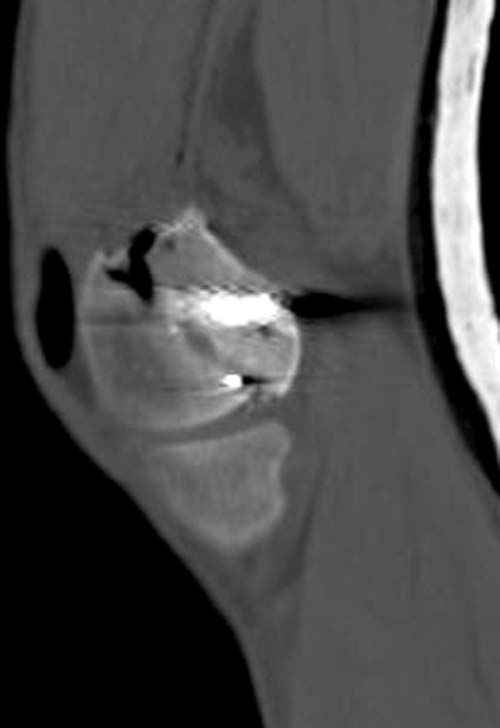

У молодого человека огнестрельное слепое ранение н/3 правого бедра. Поступил в клинику с внутрисуставным многооскольчатым Т-отразным переломом дистального отдела бедренной кости. Дополнительно на  СТ-исследовании обнаружен перелом внутреннего мыщелка Hoffa со смещением.<br><br>

Больной взят в операционную на второй день, где из небольшого медиального доступа выполнена артротомия коленного сустава. Произведена репозиция отломков, фиксация винтами. Попутно удалена пуля. Первым делом была достигнута репозиция медиального мыщелка (перелома Hoffa, где коронарная плоскость перелома трудно поддается закрытой репозиции и фиксации. ) Затем была достигнута идеальная репозиция суставной поверхности бедра и фиксация компрессирующими headless  screws.<br><br>

Дистальный отдел бедра был дополнительно фиксирован buttress пластиной с медиальной стороны из того же разреза. Для усиления фиксации латеральной колонны -  с латеральной стороны закрытым способом из минидоступа установлена еще buttress plate.  Пулевой канал дополнительно не подвергался хирургической обработке.<br><br>